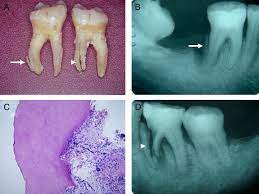

Cemental Tear An Unusual Cause For Persisting Endodontic Periodontal Lesion Chawla A Kumar V Indian J Dent Res

Cemental Tear An Unusual Cause For Persisting Endodontic Periodontal Lesion Chawla A Kumar V Indian J Dent Res from www.ijdr.in